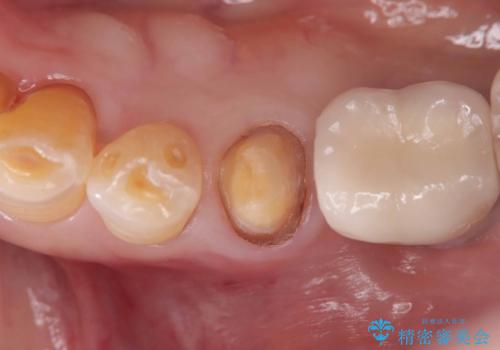

- 虫歯が原因で歯が欠けていました。昔詰めた保険の材料(CR)が劣化しその下が虫歯になっている状態でした。

色々な箇所にCR(保険の材料)を詰めてあったので、CRと虫歯を全部除去した後、オールセラミッククラウンで治療を行いました。

古いCR(保険治療で使用されるプラスチック)を除去すると残りの歯質が薄いため、破折抵抗を考慮しオールセラミッククラウンで治療を行いました。